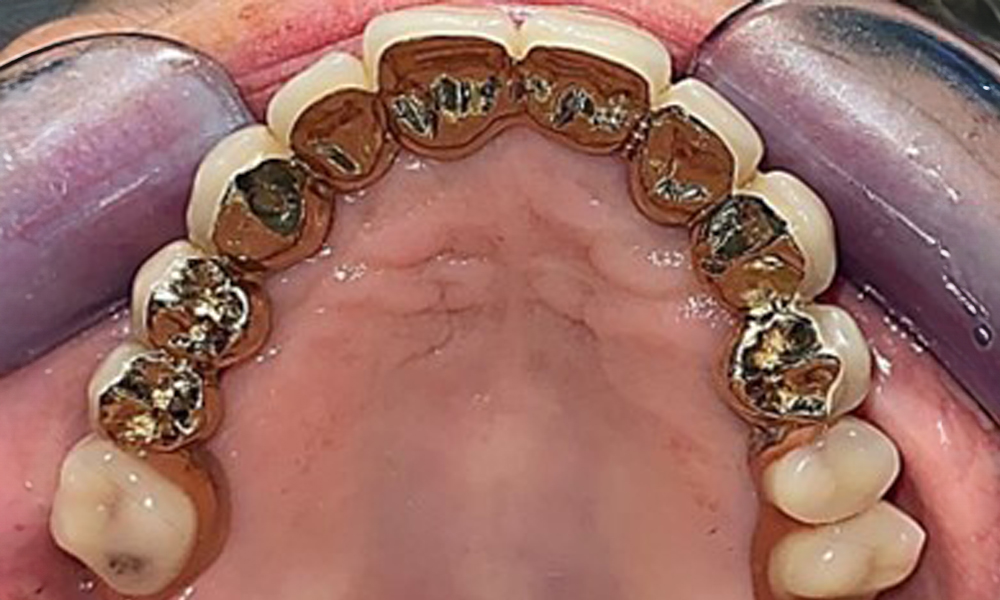

Occlusal view: Maxilla with tooth and implant-supported telescopic prostheses.

Fig. 2: Occlusal view: Maxilla with tooth and implant-supported telescopic prostheses

Occlusal view: Maxilla with removable, palateless denture.

Fig. 3: Occlusal view: Maxilla with removable, palateless denture.

The patient was fitted with a combined removable maxillary telescopic prosthesis more than 25 years ago (Fig. 1, Fig. 2, Fig. 3) and is very happy with her dentures. The patient has an adequate fixed denture for the mandible (Fig. 4).

The dental findings are as follows: Combined removable implant and tooth-supported telescopic prostheses on implants 15, 13, 21, 23, 24, 25 and tooth 11 (Fig. 1, Fig. 2, Fig. 3). The patient was fitted with a fixed mandibular denture. Adequate bridges were present over 37 to 34 and 45 to 47 (Fig. 4), the crown margins were intact and there were no active caries. A composite filling with a marginal gap was present on tooth 43. There was mandibular gingival recession, exposing 1 to 3 mm of root surface. This also applies to 11.